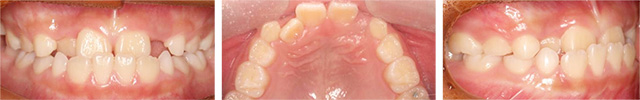

위, 아래 앞니가 거꾸로 물리는 반대교합으로 정밀진단 결과 3급 부정교합 환자 입니다. 반대교합의 경우 오랫동안 방치하게 되면 아래턱뼈의 성장이 촉진되어 시간이 흐를수록 점점 길어지기 때문에 초기에 교정하는 것이 중요합니다. 고운미소에서는 가철식 교정장치를 이용하여 앞니를 전방으로 경사이동 시키는 교정을 진행하였습니다.